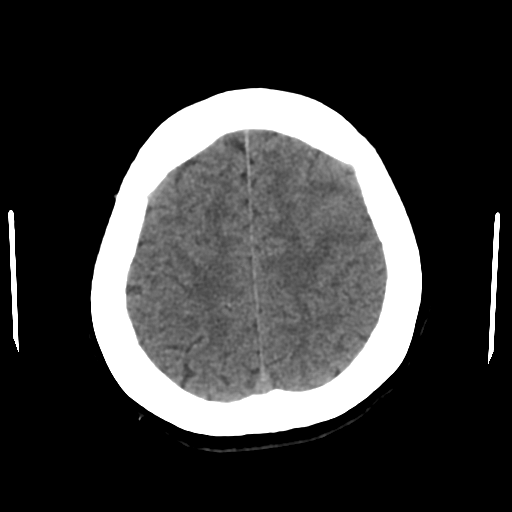

환자는 30대 여성으로 경련성 운동을 보여 응급실로 내원 하였고, 검사의 일환으로 brain CT를 촬영 했었다.

아래 3장의 사진이 환자의 brain CT 사진이다.

자 여기까지만 보면 크게 이상이 없다고 생각할 수도 있다.